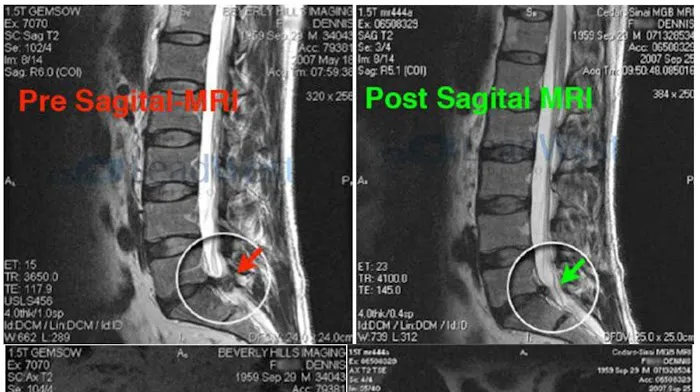

- Spinal Decompression Therapy: A primary focus of the practice, this non-surgical therapy is designed to relieve pressure on compressed spinal discs, a common cause of back and leg pain, herniated discs, and sciatica. It aims to create negative pressure within the disc, allowing for the retraction of bulging or herniated disc material and promoting nutrient flow for healing.